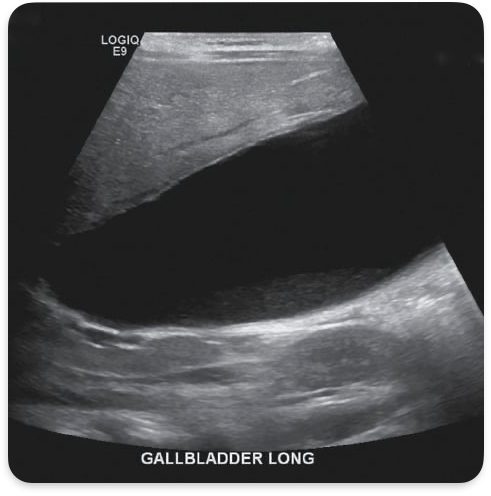

Hydropic gallbladder

Blockage of cystic duct, palpable

Hydropic gallbladder.